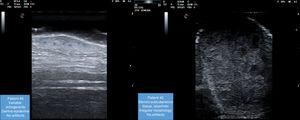

Large series have reported on the ultrasound features of cutaneous metastases from melanoma,4 but this has not been the case for metastases from visceral tumors.5,6 Moreover, most of the series that do exist have been published by radiologists and deal mainly with subcutaneous lesions (both palpable and nonpalpable). The authors of these studies stress that while cutaneous metastases do not necessarily indicate terminal disease, they are always a sign of disease spread. From an ultrasound perspective, all the lesions studied were located in the subcutaneous tissue, whereas in our series, given their accessibility, they were also observed in the epidermis and dermis. The most characteristic B-mode ultrasound finding for metastatic cutaneous lesions is an irregular, polycyclic shape, which was observed in 5 of the 6 patients in our series (Fig. 1).

Giovagnario et al.7 described 4 vascular patterns for cutaneous metastases evaluated by ultrasound: avascular, hypovascular with a single vascular pole, hypervascular with multiple peripheral poles, and hypervascular with internal vessels. All 4 patterns were observed in our series. Some authors have claimed that vascularization is highly suggestive and predictive of malignancy, with a sensitivity of 91% and a specificity of 93%.8 Avascular and hypovascular patterns may be due to lesion size, necrosis, or the presence of vessels that are too small to detect with the equipment used. This was the case with patient #6 in our series (Fig. 2).